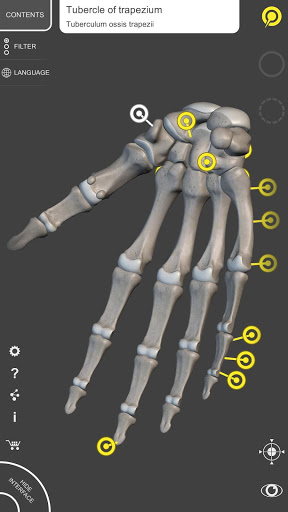

Each bone of the human skeleton has been reconstructed in 3D, you can rotate and zoom in on each model and observe it in detail from any angle.

By selecting models or pins you will be shown the terms related to any specific anatomical part, you can select from 12 languages and show the terms in two languages simultaneously.

• Accurate 3D modeling

• Surfaces of the skeleton with high resolution textures up to 4K

• Rotate and Zoom every model in the 3D space

• Interactive Pin allow visualization of the term relative to every anatomical detail